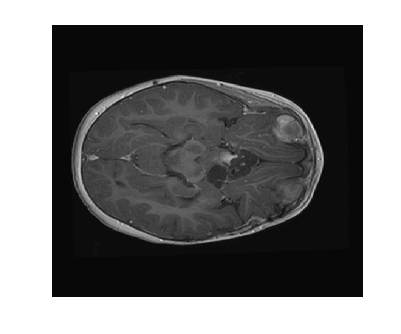

Due to its wide use in image processing, we consider the use of gradient sparsification with LACS-MRI. We show below that it is possible to produce image reconstructions with significantly higher Reconstruction SNR using gradient sparsification. We have repeated some of the simulations from above for different compression levels, , using the gradient transform to sparsify instead of the wavelet transform. We will refer to this as ”LACS-MRI with gradient sparsity.” We compared the performance of each sparsification method at each compression level using LACS-MRI and then compared this to the L1-W method. Again, we use a reference image and a follow-up image that we hope to recover as in Figure 8. We consider here only the phantom image, as it serves as a prime candidate for gradient sparsification, and is small enough that evaluation of all PDFs is computationally feasible.

Figure 12 shows the effect of a 2-fold scale difference on LACS-MRI image reconstructions. There are extensive streaking artifacts and significant detail is lost compared to the ground truth and the reconstruction using the modified method. Clearly, the Grayscale Compensation for Reference Based MRI Algorithm (GSC) can reduce these artifacts and help improve the visibility of structure.